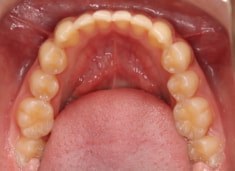

検査時のレントゲン分析では、上下顎の関係は、上顎の劣成長があり下顎前突傾向という値がでておりましたが、前歯ジャンプ後はフェイスマスクの効果もあり、上下顎の関係は正常化しています。

上顎が若干優位になっていますので、今後の下顎の成長のための貯金になっているくらいです。